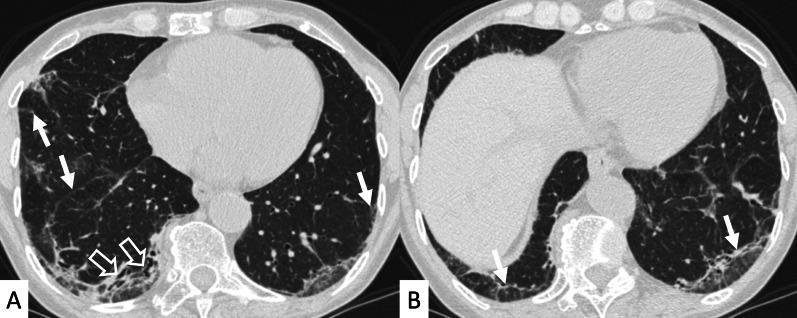

Connective tissue diseases (CTDs) include a spectrum of disorders that affect the connective tissue of the human body; they include autoimmune disorders characterized by immune-mediated chronic inflammation and the development of fibrosis. Lung involvement can be misdiagnosed, since pulmonary alterations preceded osteo-articular manifestations only in 20% of cases and they have no clear clinical findings in the early phases. All pulmonary structures may be interested: pulmonary interstitium, airways, pleura and respiratory muscles. Among these autoimmune disorders, rheumatoid arthritis (RA) is characterized by usual interstitial pneumonia (UIP), pulmonary nodules and airway disease with air-trapping, whereas non-specific interstitial pneumonia (NSIP), pulmonary hypertension and esophageal dilatation are frequently revealed in systemic sclerosis (SSc). NSIP and organizing pneumonia (OP) may be found in patients having polymyositis (PM) and dermatomyositis (DM); in some cases, perilobular consolidations and reverse halo-sign areas may be observed. Systemic lupus erythematosus (SLE) is characterized by serositis, acute lupus pneumonitis and alveolar hemorrhage. In the Sjögren syndrome (SS), the most frequent pattern encountered on HRCT images is represented by NSIP; UIP and lymphocytic interstitial pneumonia (LIP) are reported with a lower frequency. Finally, fibrotic NSIP may be the interstitial disease observed in patients having mixed connective tissue diseases (MCTD). This pictorial review therefore aims to provide clinical features and imaging findings associated with autoimmune CTDs, in order to help radiologists, pneumologists and rheumatologists in their diagnoses and management.

结缔组织病(CTDs)包括一系列影响人体结缔组织的疾病;它们包括以免疫介导的慢性炎症和纤维化发展为特征的自身免疫性疾病。肺部受累可能会被误诊,因为肺部改变仅在20%的病例中先于骨关节炎表现出现,且在早期阶段没有明确的临床发现。所有肺部结构都可能受累:肺间质、气道、胸膜和呼吸肌。在这些自身免疫性疾病中,类风湿关节炎(RA)的特征是普通型间质性肺炎(UIP)、肺结节和伴有空气潴留的气道疾病,而系统性硬化症(SSc)常表现为非特异性间质性肺炎(NSIP)、肺动脉高压和食管扩张。NSIP和机化性肺炎(OP)可见于多发性肌炎(PM)和皮肌炎(DM)患者;在某些情况下,可观察到小叶周围实变和反晕征区域。系统性红斑狼疮(SLE)的特征是浆膜炎、急性狼疮性肺炎和肺泡出血。在干燥综合征(SS)中,HRCT图像上最常见的表现是NSIP;UIP和淋巴细胞间质性肺炎(LIP)的报道频率较低。最后,纤维化NSIP可能是混合性结缔组织病(MCTD)患者中观察到的间质性疾病。因此,本图像综述旨在提供与自身免疫性CTDs相关的临床特征和影像学表现,以帮助放射科医生、呼吸科医生和风湿病科医生进行诊断和管理。